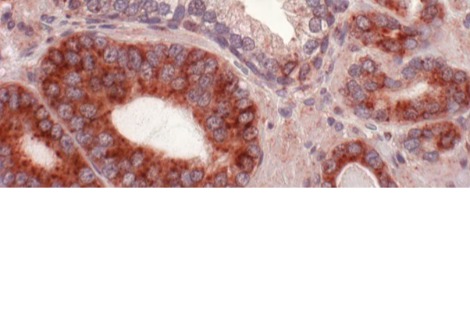

شهدت العقود القليلة الماضية زيادة سريعة في أنواع الفطريات التي تسبب التهابات حادة لدى البشر. ومن الأمثلة على الفطريات التي يصعب علاجها فطر المبيضات أوريس (C. auris).

أوضح تومسون قائلاً: "تمتلك الفطريات آليات خلوية مشابهة لتلك الموجودة لدى البشر. ولهذا السبب، غالباً ما تُسبب الأدوية التي تقتل الفطريات، مثل كانديدا أوريس، آثاراً جانبية على البشر. ومع قلة مضادات الفطريات المتاحة أثناء الرعاية السريرية، فإن منع المقاومة أمر بالغ الأهمية".